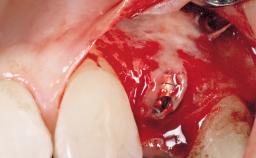

Early Placement of an Implant in a Maxillary Right Central Incisor Site

Bone Augmentation Horizontal|Simultaneous

Augmentation Materials Autogenous chips|Xenogenous|Membrane

Bone Volume Deficient horizontally, allowing simultaneous augumentation